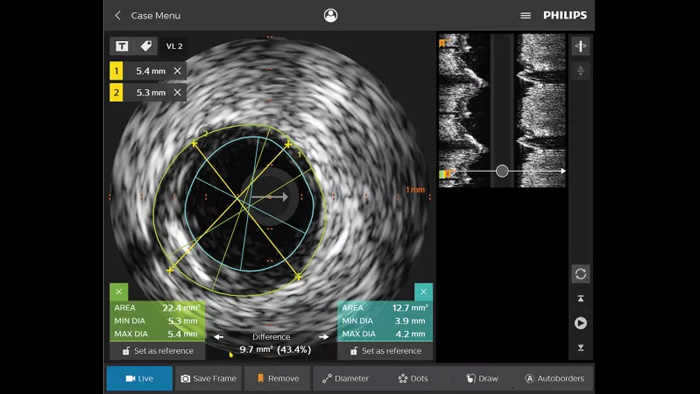

La ecografía intravascular (EIV) es una tecnología de imágenes basada en catéteres que permite a los médicos ver los vasos sanguíneos de adentro hacia afuera para ayudar a evaluar la presencia y el alcance de la enfermedad. La EIV ayuda a decidir, guiar y confirmar el tratamiento intervencionista adecuado para cada paciente.

IntraSight proporciona más información a través de las modalidades iFR/FFR y EIV junto con el control del angiograma desde la pantalla táctil de la mesa. Se basa en una plataforma fundamental capaz de agregar rápidamente nuevas innovaciones a su laboratorio.